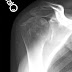

A 60 year old physician presented to us with a painful stiff shoulder and these films.

Because of his desired activity levels, he wished to avoid the polyethylene glenoid component used in a conventional total shoulder; therefore he elected a ream and run procedure. After surgery he used his

electric toothbrush to time his 2 minute stretches several times per day.. Today he returned for followup 6 years after his ream and run with a comfortable, functional shoulder and excellent motion.His x-rays at 6 years after surgery show secure fixation of his impaction grafted humeral prosthesis and a regenerated stable bearing surface on his glenoid.